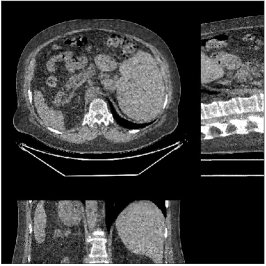

We reconstructed the abdomen volume from low-dose helical CT data. With an initialization of zeros, we ran the PWLS-EP algorithm with and for iterations with subsets for the mA and mA scans, respectively. For PWLS-ULTRA, we chose for the mA scan, for the mA scan, and ran it for outer iterations. The other parameter settings and the transform were the same as those used for the chest scan.

Fig.Β 10 shows the reconstructions (shown for the central axial, sagittal, and coronal planes in the 3D volume) for PWLS-EP and PWLS-ULTRA with patch-based weights () from low-dose abdomen scans. For the sagittal and coronal planes, we show the central out of axial slices. The supplement provides PWLS-EP reconstructions with different regularization strengths. The PWLS-ULTRA reconstructions in Fig.Β 10 have reduced noise as well as higher resolution, better structural details and shaper image edges than the PWLS-EP results. These results are further example of the potential performance of the proposed PWLS-ULTRA method in clinical settings.